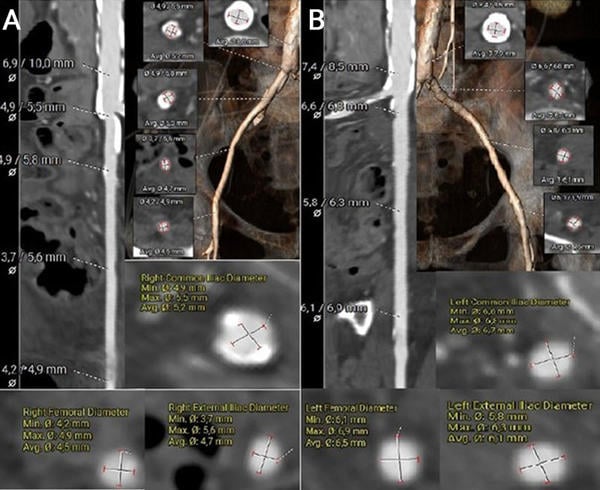

The left common femoral artery measured 6.1 × 6.9 mm, suggesting potential suitability for transfemoral access. In contrast, the right common femoral artery measured 4.2 × 4.9 mm, and the right common iliac artery measured 4.9 mm in diameter. However, the presence of extensive circumferential calcification in the right iliac artery significantly limits its feasibility for vascular access (Figures 3A–B).

Figure 3. MSCT vascular access measurements using the 3mensio software

(A) Measurement and visualisation of the right common femoral artery, right external iliac artery, and right common iliac artery, including a segment of the descending aorta.

(B) Measurement and visualisation of the left common femoral artery, left external iliac artery, and left common iliac artery, including a segment of the descending aorta.